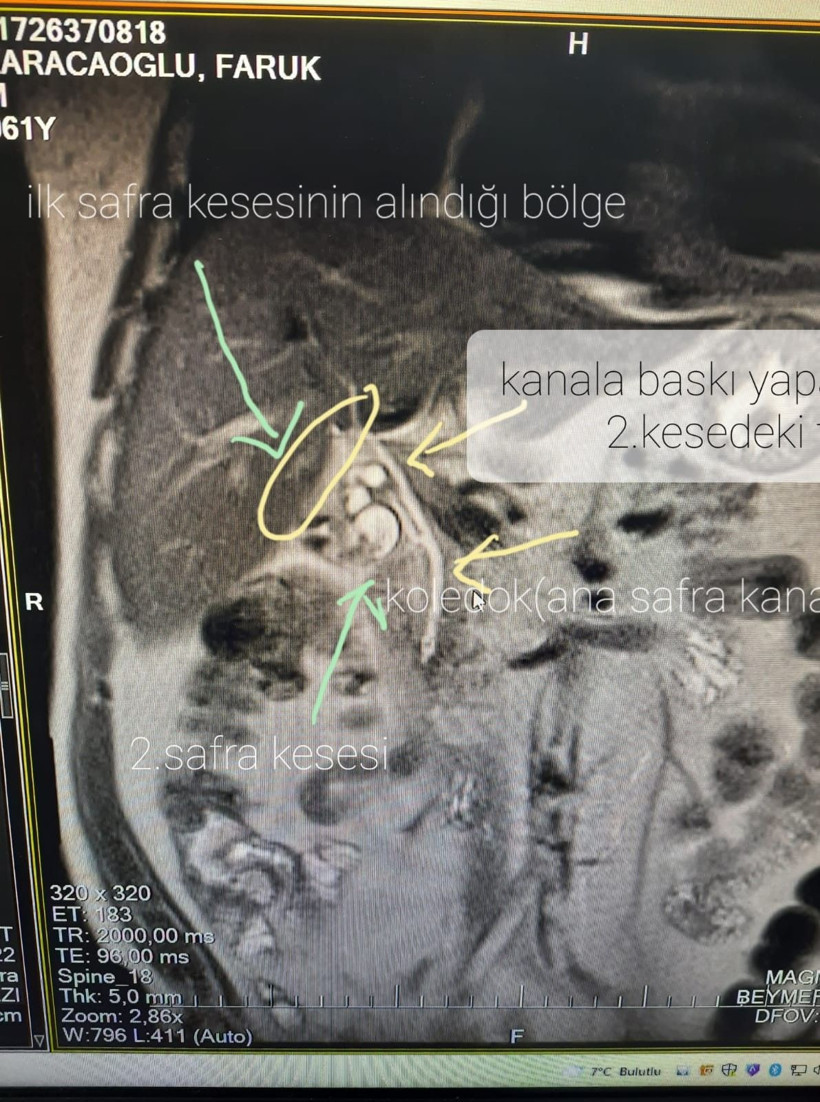

13 yıl önce safra kesesinden ameliyat geçiren Faruk Karacaoğlu, 2 yıl sonra öğrendikleri ile şoke oldu. 2 yılda 15 doktor tarafından farklı tedavi gören hasta, ikinci bir safra kesesinin olduğunu öğrendi. Safra kesesi alındığı için yıllarca ilaç tedavileriyle geçiştirilen hasta, tespit edilen ikinci safra kesesinin de ameliyatla alınmasıyla sağlığına kavuştu.

Son 2 yıldan bu yana 15 doktora giderek ağrılarından kurtulmaya çalışan hasta, Genel Cerrahi Uzmanı Ahmet İmdat Koçberber tarafından yapılan muayenesinde ikinci bir safra kesesi olduğunu öğrenince şok oldu. Faruk Karacaoğlu, yapılan başarılı operasyonun ardından hasta sağlığına kavuştu.